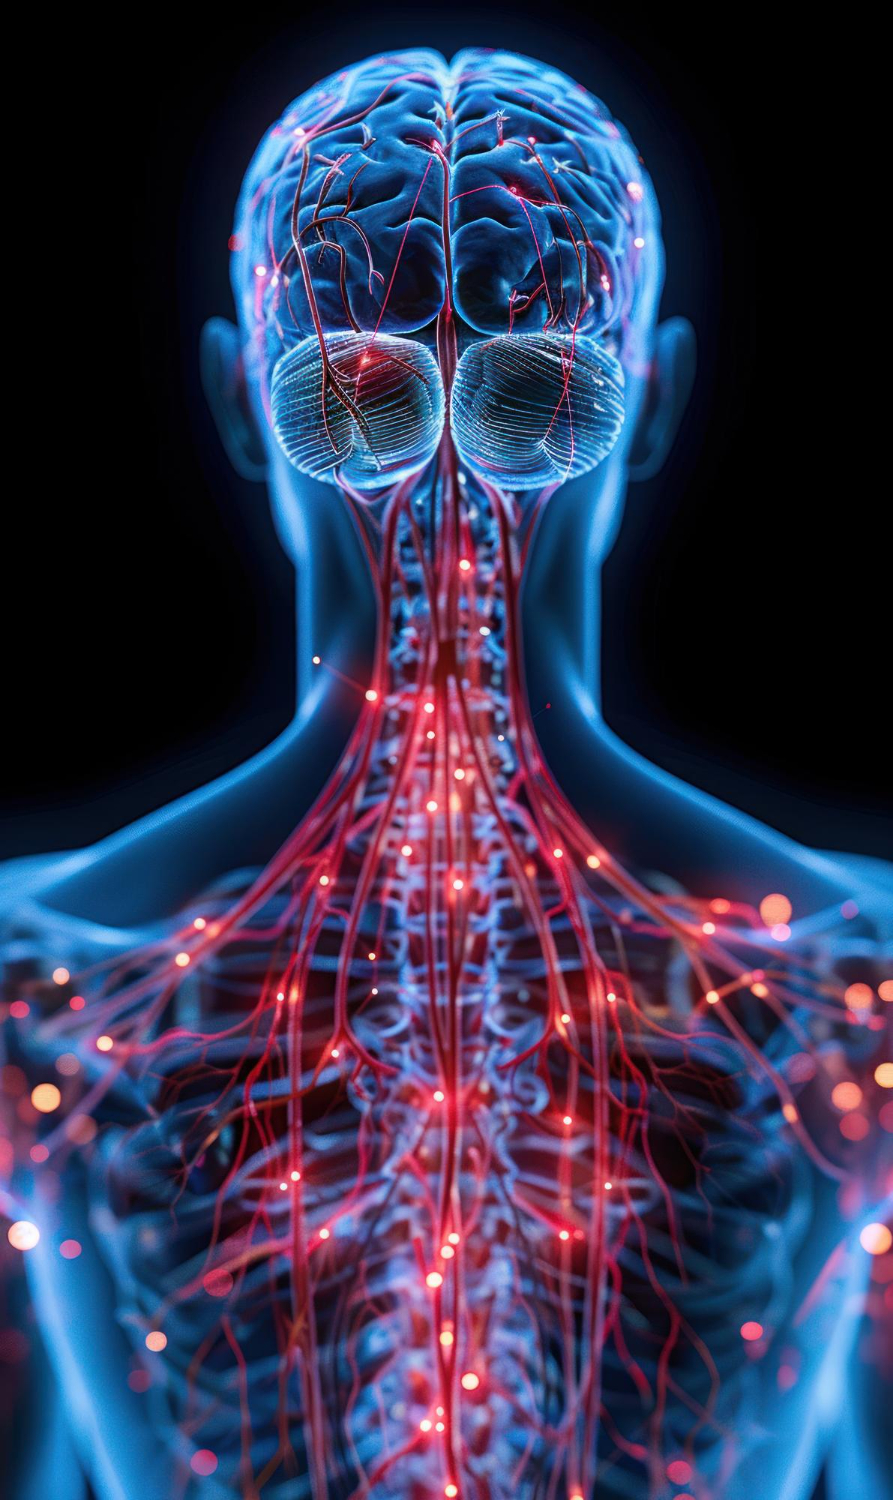

Tumores de nervos periféricos

A espondilolistese é uma condição em que uma vértebra da coluna desliza sobre a outra, podendo causar dor lombar, fraqueza, formigamento e limitação de movimentos. O diagnóstico precoce é essencial para evitar a progressão do quadro e definir o tratamento mais adequado. Na Clínica N3, oferecemos avaliação especializada e acompanhamento personalizado, com opções de tratamento clínico e cirúrgico, sempre com foco em aliviar os sintomas, restaurar a função e garantir qualidade de vida ao paciente.

Segurança e experiência no cuidado de tumores neurológicos

A Clínica N3 é referência no diagnóstico e tratamento de tumores cerebrais, da medula espinhal e de nervos periféricos, oferecendo acompanhamento completo e personalizado para cada paciente. Com uma equipe de profissionais altamente qualificados em neurologia e neurocirurgia, aliamos experiência, tecnologia avançada e cuidado humanizado em todas as etapas do tratamento. Nosso compromisso é proporcionar segurança, eficácia e qualidade de vida, consolidando a Clínica N3 como um centro de excelência em Londrina e região.